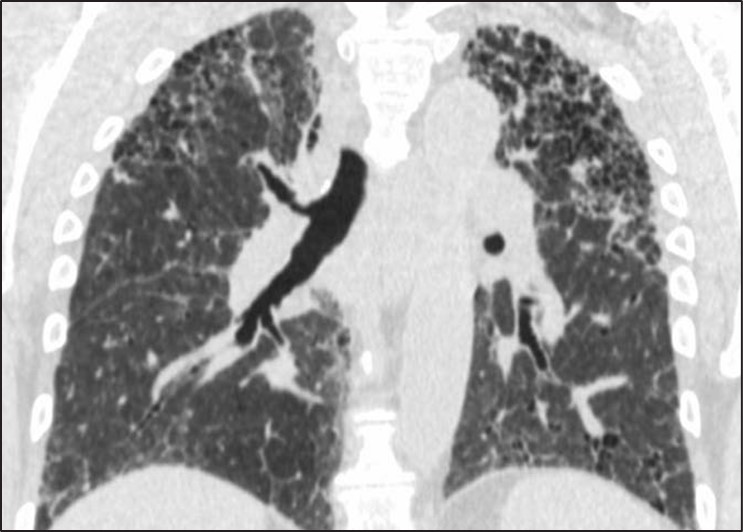

Fig. 5—Fibrosis with honeycombing in atypical distribution. Left, Axial HRCT scan shows diffuse fibrosis in association with ground-glass opacity. Diagnosis was hypersensitivity pneumonitis. Right, Coronal HRCT scan shows upper lobe–predominant fibrosis. Diagnosis was sarcoidosis.

Fibrosis that is diffuse in the axial plane or predominately in an upper lung, central, or peribronchovascular distribution may indeed be associated with honeycombing but nonetheless be caused by other entities such as nonspecific interstitial pneumonia, sarcoidosis, or hypersensitivity pneumonitis [11, 12]. Subpleural and basal distribution of fibrosis is essential to describing a pattern of fibrosis consistent with UIP at imaging. A percentage of cases with atypical distributions of fibrosis and honeycombing may be subsequently identified as UIP after biopsy; however, these cases are exactly those that benefit from surgical lung biopsy because there is a relatively high chance (70%) that another diagnosis will be found [12, 13].